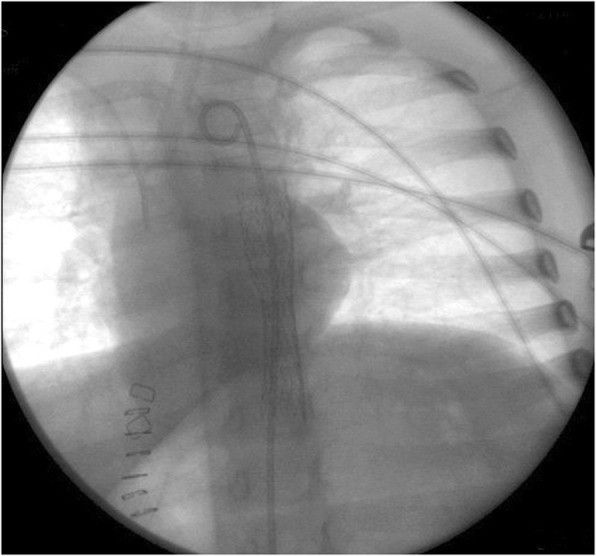

Через 6 часов у пациентки возникла массивная рвота кровью и тяжелый гиповолемический шок. Попытка проведения эзофагогастроскопии оказалась неудачной из-за большого количества крови и сгустков в пищеводе и желудке. Потребовалась лапаротомия, в ходе которой батарея была извлечена, но, несмотря на это, кровотечение продолжалось, состояние пациентки оставалось крайне тяжелым. С гемостатической целью девочке был установлен зонд Сенгстакена — Блэкмора. Но при повторном эндоскопическом исследовании выявлено, что источник кровотечения расположен в средней трети пищевода (рис. 2 — A).

Рисунок 2 [1].

Эндоскопическое исследование через год показало полную реэпителизацию на месте кровотечения из пищевода (рис. 2 — B). Наблюдение в течение трех лет не выявило каких-либо осложнений.